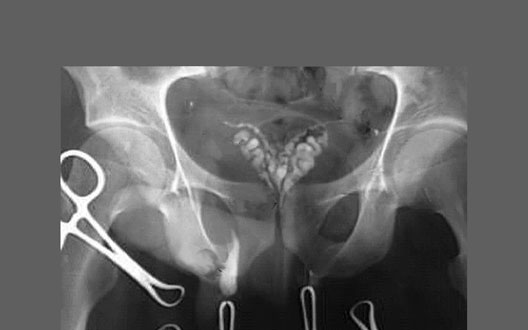

Vasogram

1. Ductus deferens

2. Seminal vesicle

3. Prostatic urethra

4. Extravasation of contrast material